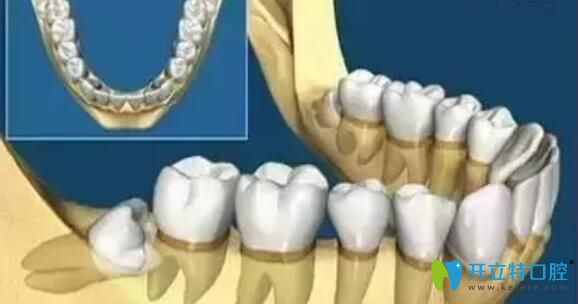

牙齒在頜骨內(nèi)由于位置不正,不能萌出到正常的咬合位置,這樣的牙齒稱為阻生牙。常見的阻生齒是下頜第三磨牙(智齒),其次是上頜第三磨牙(智齒)和上頜尖牙。所以阻生牙不一定是智齒,也可能是其它牙齒,如果智齒萌出正常,則不能稱為阻生牙。

阻生牙是因?yàn)樯L的位置不當(dāng),因此往往會(huì)以很多“出人意料”的姿勢生長,這種使得牙齒之間很容易藏污納垢和滋生細(xì)菌,并且很容易引起口臭、齲壞等,如果是阻生智齒,宜盡早拔除,以下情況建議拔除。